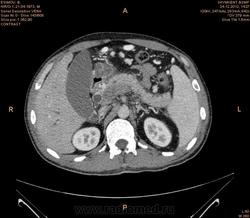

Предварительно образование головки ПЖ, и в печени. Что с ферментами?

на операций рак головки подж.железы с метастазир. печень.

инфильтрация тут нисходящей 12 перст кишки , расширенного холедох,расширенный вирсунгов проток ,нижная граница очень близко прилежит к нижней полой вене с правой почечной веной ,но четко визуализирутся передний листок фасции Героты(нельзя исключить ее инфильтрацию), инфильтрация конгломератом увеличенных лимфатических узлов ворот печени портальной вены с варикозным расширением вен, на вышележащий срезах четко определяются верхняя брыжеечная вена и артерия ,не хватает срезов для полной визуализации(помогли бы мпр),инфильтрирована восходящая ободочная кишка,конгломерат лимфат узлов за головкой поджелудочной железы в виде гиподенсивного участка вытянутой формы , ,мтс в печень,парааортальные